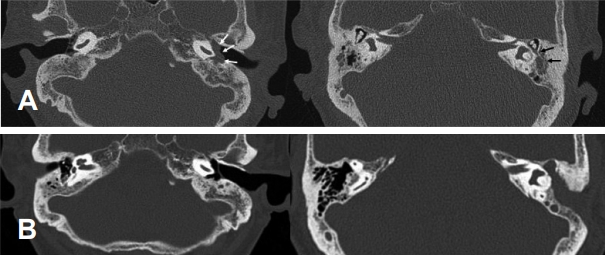

56세 여자 환자가 수일 전부터 발생한 회전성 어지럼증을 주소로 응급실에 내원하였다. 병력상 3달 전부터 양측 이충만감이 발생하였고, 내원 2달 전 개인병원에서 양측 삼출성 중이염으로 진단받고 양측 모두 고막환기관을 삽입하였다. 내원 이틀 전 좌측 이통이 악화되어 고막환기관은 제거하였고, 비슷한 시기에 회전성 어지럼이 발생하여 응급실로 내원하였다. 응급실에서 시행한 이학적 검사상 우측으로 자발안진이 관찰되었고, 환자는 인지하지 못하였지만 House-Brackmann grade III의 우측 안면신경마비 소견이 함께 관찰되었다. 고막 검진상 우측 고막환기관 및 양측 장액성 이루가 관찰되었고 순음 청력검사에서 우측 45 dB, 좌측 기도청력 66 dB, 골도청력 58 dB로 측정되었다(Fig. 3). 측두골 전산화단층촬영에서는 좌측 중이강 내에 연조직 음영이 관찰되며 유양돌기에도 염증 소견이 관찰되었다(Fig. 4A). 안면마비에 대해 고용량 스테로이드(methylprednisolone 48 mg) 치료를 시작하였고, 어지럼증에 대해 시행한 caloric검사상 좌측은 반응이 나타나지 않았고, 우측으로 자발안진이 관찰되어 좌측 전정기능장애 소견이 관찰되었다. 내이도 자기공명영상에서는 우측 안면신경을 일으킬 만한 특별한 병변은 관찰되지 않았다. 2주간 고용량 스테로이드 치료를 시행한 후 3일째 환자는 좌측 이통 및 이루가 악화되어 다시 응급실로 내원하였고, 증상 조절을 위해 입원하였다. 이루에 대해서 시행한 균배양검사에서 동정되는 균은 없었다. 입원하여 시행한 면역검사상 MPO-ANCA는 양성이었으며 PR3-ANCA는 음성 소견을 보였다. 함께 시행한 비강 및 인, 후두 내시경에서는 특별한 이상 소견은 관찰되지 않았다. 가슴 방사선검사상 기관지 확장증이 의심되어 가슴 전산화단층촬영을 시행하였으며, 폐 실질에는 특별한 이상 소견이 없고 특별한 호흡기 증상이 없는 상태로 경과 관찰하기로 하였다. 시행한 혈액검사상 혈청 크레아티닌 수치도 0.68 mg/dL로 정상이었다. 내과 협진하에 prednisolone 1 mg/kg/day 및 methotrexate 10 mg/week, folic acid 1 mg/day를 유지하며 경과 관찰하던 중 투약 이후에도 좌측 이통 및 이루가 악화되어 투약 이틀째 병변의 재평가를 위해 측두골 전산화단층촬영을 시행하였으며, 검사상 이전보다 좌측 중이강 내 병변의 범위가 증가하는 소견이 보여 수술적 치료를 계획하였다. 전신마취하에 좌측 폐쇄형 유양동 삭개술(intact canal wall mastoidectomy)을 시행하고, 중이강 내의 육아조직을 제거한 후 침골 및 추골의 두부를 제거하고 이소골의 재건 없이 제0형 고실성형술(tympanization)을 시행하였다[6]. 조직검사상 뚜렷한 혈관염의 소견은 확인되지 않았다. 수술 후에도 스테로이드는 유지하였으며, 이통 및 이루는 호전되어 환자는 수술 후 9일째 퇴원하였다. 한 달 후 우측 안면신경마비는 정상으로 호전되었고, 이후 환자는 정기적으로 류마티스 내과 및 이비인후과 외래를 통해 증상에 따라 스테로이드 용량을 조절하였으며, 18개월간 투약 후 스테로이드는 중단한 상태로 특이 증상 없이 외래 통한 경과 관찰 중이다. 수술 후 1년 6개월째에 시행한 측두골 전산화단층촬영에서 중이강 내에 연조직 음영은 모두 호전된 상태로(Fig. 4B), 좌측에 대하여 2차 이소골 성형술을 시행하였다. 회복 후 시행한 순음 청력검사상에서 우측 22 dB, 좌측 기도청력 43 dB, 골도청력 21 dB로 호전된 소견이 관찰되었다(Fig. 3).